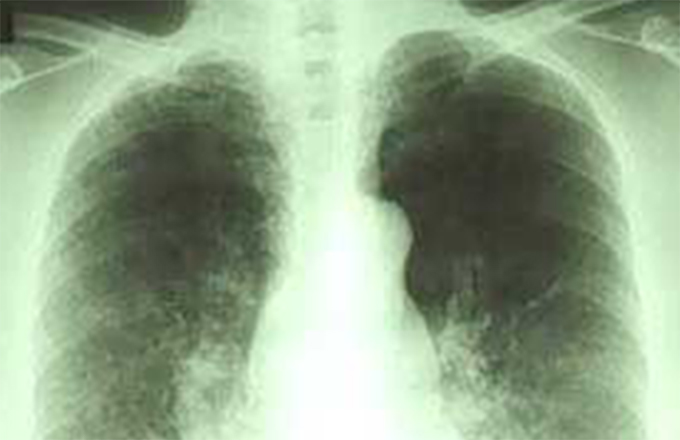

概要・特色呼吸器科では、のどや気管支、肺の病気を診療しています。医療の進歩はこの領域でも近年の治療法の進歩により、多くの病気の患者さんに、症状の改善が期待できるようになりました。

呼吸器科では、のどや気管支、肺の病気を診療しています。医療の進歩はこの領域でも近年の治療法の進歩により、多くの病気の患者さんに、症状の改善が期待できるようになりました。